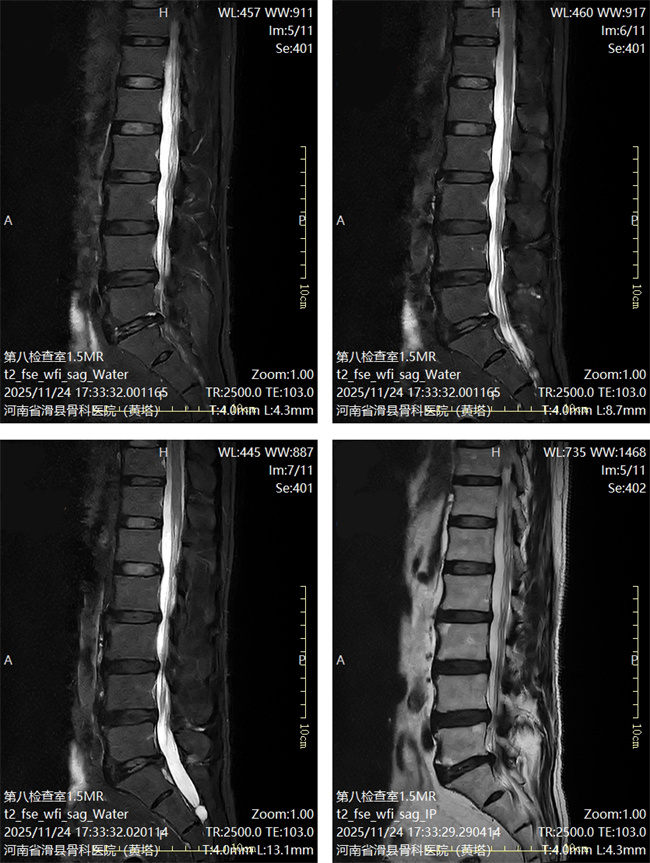

一、患者付某某,男,71岁,患者腰部及右髋部疼痛2年余,加重伴右小腿麻木10天,活动受限。为求进一步治疗,来到我院请专家会诊,通过各位专家会诊查体、查看影像资料并细致认真的分析后,意见:对症保守治疗。